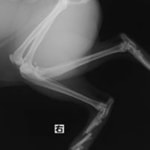

症例:交通事故による椎体脱臼

柴犬:9歳、避妊雌

交通事故直後、胸腰部に激しい疼痛、両後肢に完全麻痺を認め、シェフシェリントン徴候を呈していました。レントゲン検査において、第11-12胸椎間の脱臼が認められました。

脊髄の減圧、脊柱管の再構築・安定化を目的に、片側椎弓切除術およびMatrixMANDIBLE Plateによる椎体固定を実施しました。

隣接椎体を架橋するようにプレートを設置しました。

術後レントゲン写真